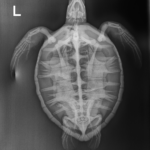

juvenile green sea turtle weighing 4.4lbs

Patient Injuries

Minor abrasion on carapace, plastron, rear flippers and tail

In-house PCV = 24%, TP = 2.4 g/dl, glucose = 166. Started on Ceftaz, Vit B, and Normosol.